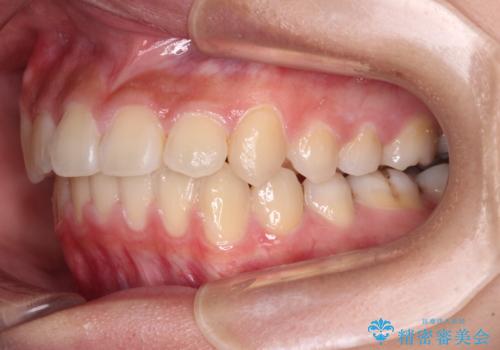

- 下顎の前突感と前歯の叢生を気にして来院された患者様です。

下顎前方位の骨格のため、下顎歯列に対して上顎歯列の幅が狭くなっていました。

上顎骨を拡大しない場合には、奥歯に咬みにくさが残ったり、下顎前歯の歯肉退縮や口元の突出感などが出たりと、妥協的な仕上がりとなります。